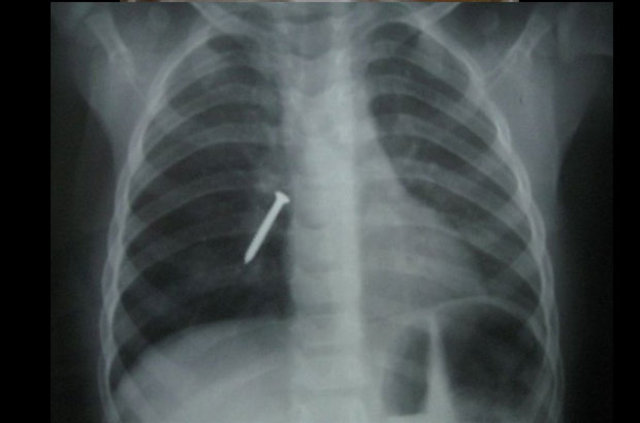

Genellikle yabancı cisimler 'X' ışınıyla görülebilir. Direk grafi ile metal ve 'X' ışınına duyarlı cisimleri rahatlıkla görebiliyoruz. Ama plastikleri göremiyoruz. Bu durumda oyuncağın bir parçasıyla yutulan parçayı anlamaya çalışıyoruz."

Cumhuriyet Üniversitesi (CÜ) Tıp Fakültesi Araştırma ve Uygulama Hastanesi Göğüs Cerrahisi Anabilim Dalı Servisi'nde insanların yanlışlıkla yuttuğu cisimlerden oluşturulan koleksiyon, görenleri hayrete düşürüyor.

Operasyonla mideden ya da nefes borusundan çıkan parçalar zaman zaman hekimleri bile şaşırtıyor.

Aralarında iğne, metal kolye, vida, protez diş, dikiş iğnesi, kemik parçası, pisi pisi otu, çivi ve akasya dikeni de bulunan cisimleri koleksiyon yapan hekimler, vatandaşların ağızlarına aldıkları şeylere dikkat etmeleri gerektiğini dile getiriyor.